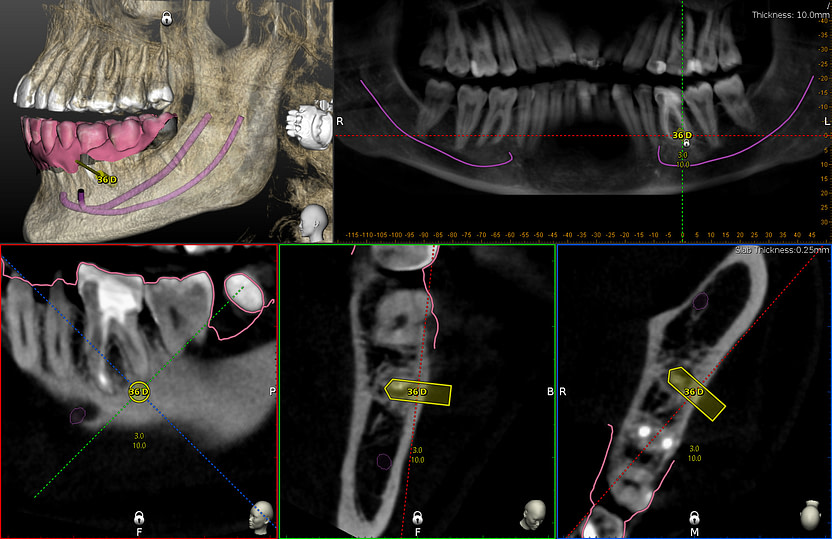

The second case was an apicectomy of lower molar 36 distal root. This would normally be a very difficult procedure to do due to poor visibility, difficulty to visualise the 3D position of the root apex. However this procedure was completed with high accuracy and efficiency.

CBCT and intraoral scans are aligned together. Planned to use trephine drill to create window through cortical bone as well as remove the 36D root tip. Axis and depth of the osteotomy are designed with the included planning software.

Live navigation of trephine drill. I had to alter the axis slightly due to difficult access. However the tip of the drill reached the planned location and depth.